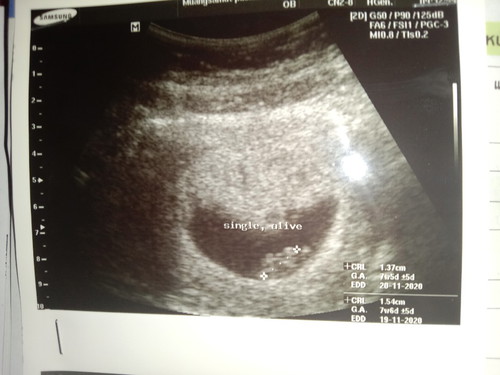

ท้องสองค่ะ อายุครรภ์ในใบซาวด์เชื่อถือได้มากน้อยแค่ไหนค่ะ เพราะแม่จำวันสุดท้ายที่ปจด.มาไม่ได้ค่ะ